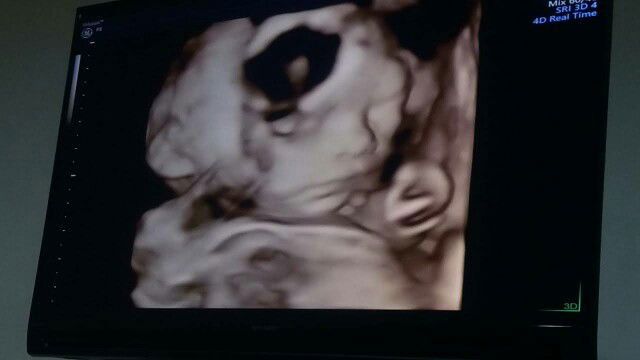

kemarin sy usg 4d 13w sudah diperkirakan jk cowok, terakhir 4d 19w masih cowok. Insya Allah jelas bgt, jd alhamdulillah dedeknya ga ngumpetin jk โบ๏ธ

saya udah keliatan usia janin 14mgg pake Usg 4D.. sekarang udah usia 35mgg JKnya sama